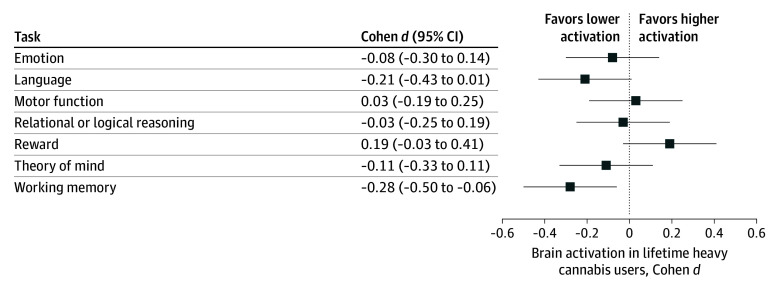

For graphical comparison, we calculated effect sizes (Cohen d) for activation during each task by (1) lifetime history of use (heavy users vs nonusers), (2) recent use (THC-positive vs THC-negative result), and (3) cannabis diagnosis (history vs no history of dependence). We report comparisons between nonusers and moderate users, as well as heavy users and moderate users, in eFigures 2 and 3 in Supplement 1.

Although there were no linear associations between lifetime history of cannabis use and task activation after adjusting for associations with recent use, there were significant quadratic effects (β = −4.54 [95% CI, −7.55 to −1.54]; P = .003 and Benjamini-Hochberg adjusted P = .02), such that greater use was associated with lower activation (full statistical models are shown in eTables 1-7 in Supplement 1). The association between lifetime history of use and theory of mind task activation did not survive correction for multiple comparisons. A summary of effect sizes for brain activation among lifetime heavy users vs nonusers is illustrated in Figure 2; the largest effect size (Cohen d = −0.28 [95% CI, −0.50 to −0.06]; false discovery rate corrected P = .02) was observed for the working memory task. Central tendency by group is reported for each task in eTable 8 in Supplement 1.